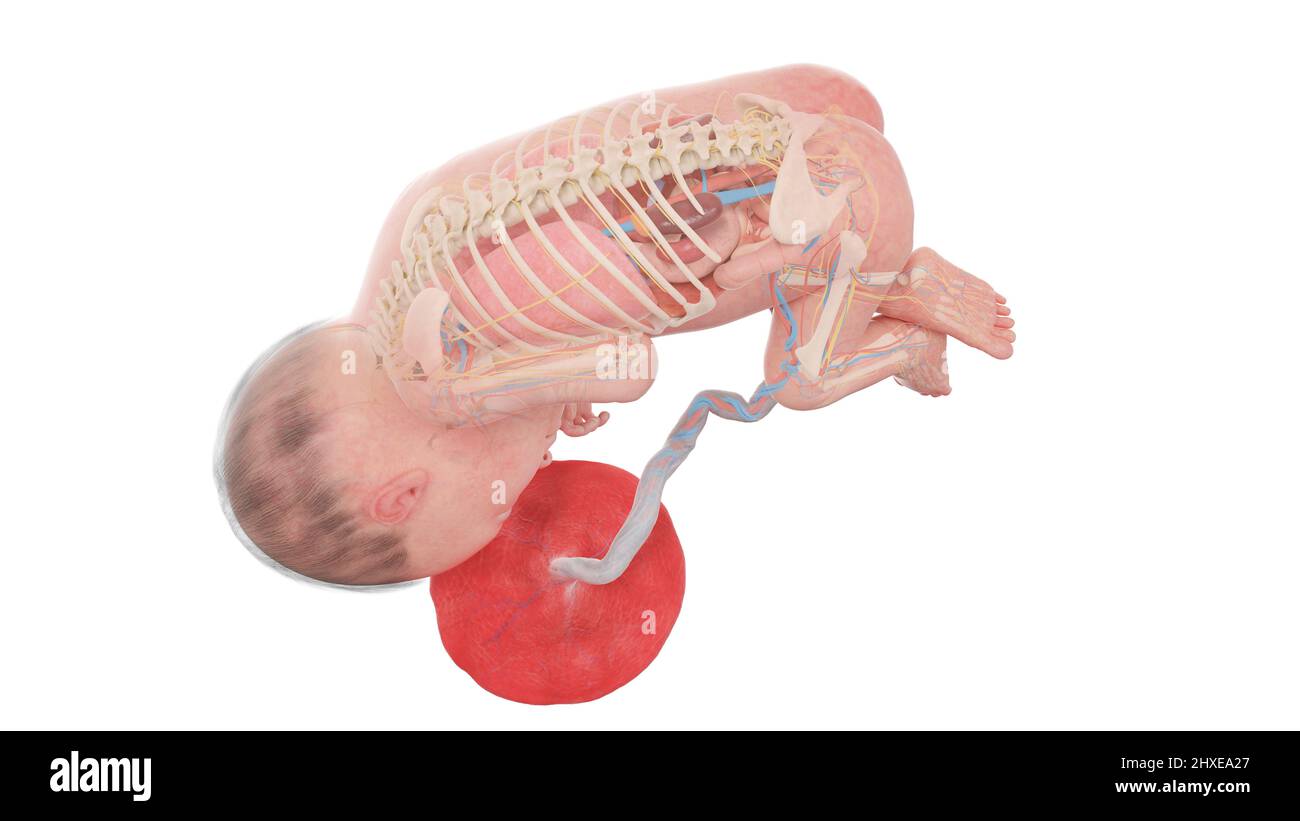

Anatomia del feto umano alla settimana 27, illustrazione Foto Stockhttps://www.alamy.it/image-license-details/?v=1https://www.alamy.it/anatomia-del-feto-umano-alla-settimana-27-illustrazione-image463765763.html

Anatomia del feto umano alla settimana 27, illustrazione Foto Stockhttps://www.alamy.it/image-license-details/?v=1https://www.alamy.it/anatomia-del-feto-umano-alla-settimana-27-illustrazione-image463765763.htmlRF2HXE9XY–Anatomia del feto umano alla settimana 27, illustrazione

Feto umano alla settimana 27, illustrazione Foto Stockhttps://www.alamy.it/image-license-details/?v=1https://www.alamy.it/feto-umano-alla-settimana-27-illustrazione-image463765837.html

Feto umano alla settimana 27, illustrazione Foto Stockhttps://www.alamy.it/image-license-details/?v=1https://www.alamy.it/feto-umano-alla-settimana-27-illustrazione-image463765837.htmlRF2HXEA1H–Feto umano alla settimana 27, illustrazione